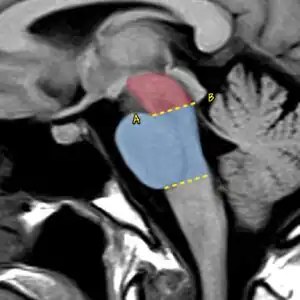

![]() | |

| In PSP the midbrain (red) to pons area (blue) ratio is typically reduced to 0.12[3] | |

MRI is often done to diagnose PSP. MRI may show atrophy in the midbrain with preservation of the pons giving a "hummingbird" sign appearance and Mickey Mouse sign.[32]